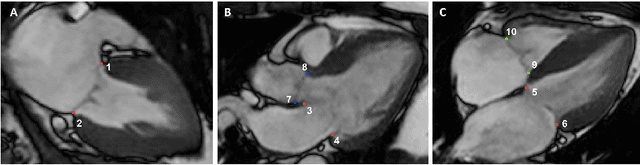

Valve annuli motion and morphology, measured from non-invasive imaging, can be used to gain a better understanding of healthy and pathological heart function. Measurements such as long-axis strain as well as peak strain rates provide markers of systolic function. Likewise, early and late-diastolic filling velocities are used as indicators of diastolic function. Quantifying global strains, however, requires a fast and precise method of tracking long-axis motion throughout the cardiac cycle. Valve landmarks such as the insertion of leaflets into the myocardial wall provide features that can be tracked to measure global long-axis motion. Feature tracking methods require initialisation, which can be time-consuming in studies with large cohorts. Therefore, this study developed and trained a neural network to identify ten features from unlabeled long-axis MR images: six mitral valve points from three long-axis views, two aortic valve points and two tricuspid valve points. This study used manual annotations of valve landmarks in standard 2-, 3- and 4-chamber long-axis images collected in clinical scans to train the network. The accuracy in the identification of these ten features, in pixel distance, was compared with the accuracy of two commonly used feature tracking methods as well as the inter-observer variability of manual annotations. Clinical measures, such as valve landmark strain and motion between end-diastole and end-systole, are also presented to illustrate the utility and robustness of the method.